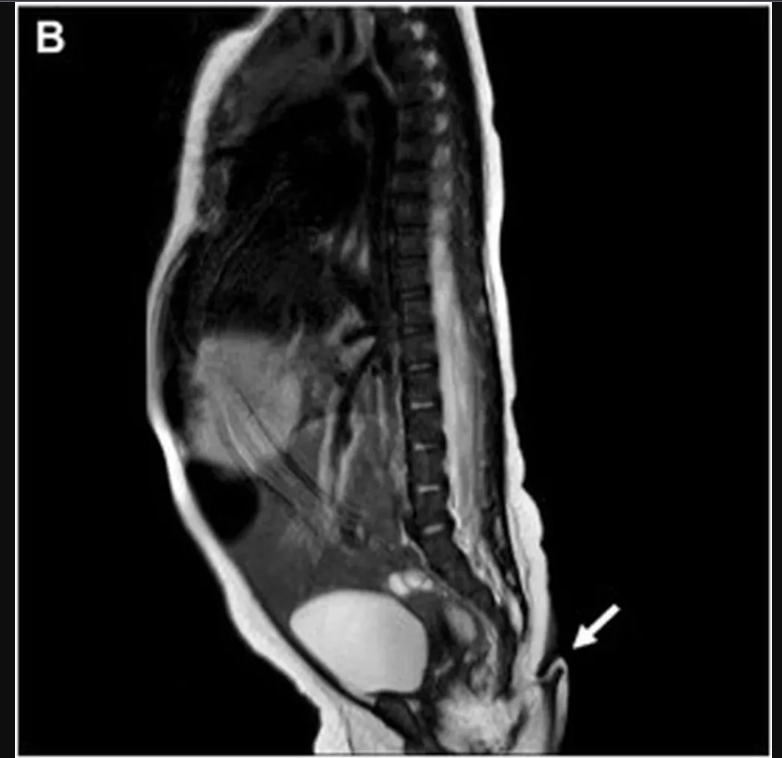

El Journal indicó que, tras hacerle una radiografía, el personal médico no encontró ninguna evidencia de anomalías o estructuras óseas en su interior. La beba tampoco presentó problemas cardíacos o auditivos, malformaciones del tracto urinario, anomalías cerebrales y tampoco malformaciones de la columna.